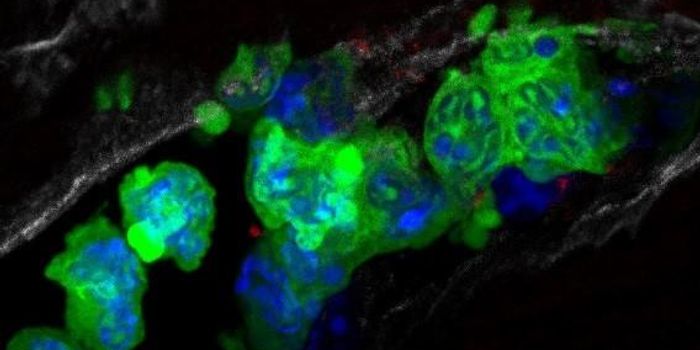

AUG 15, 2017CancerTo creep into distant parts of the body, some cancer cells have developed a knack for shapeshifting – morphing on ...